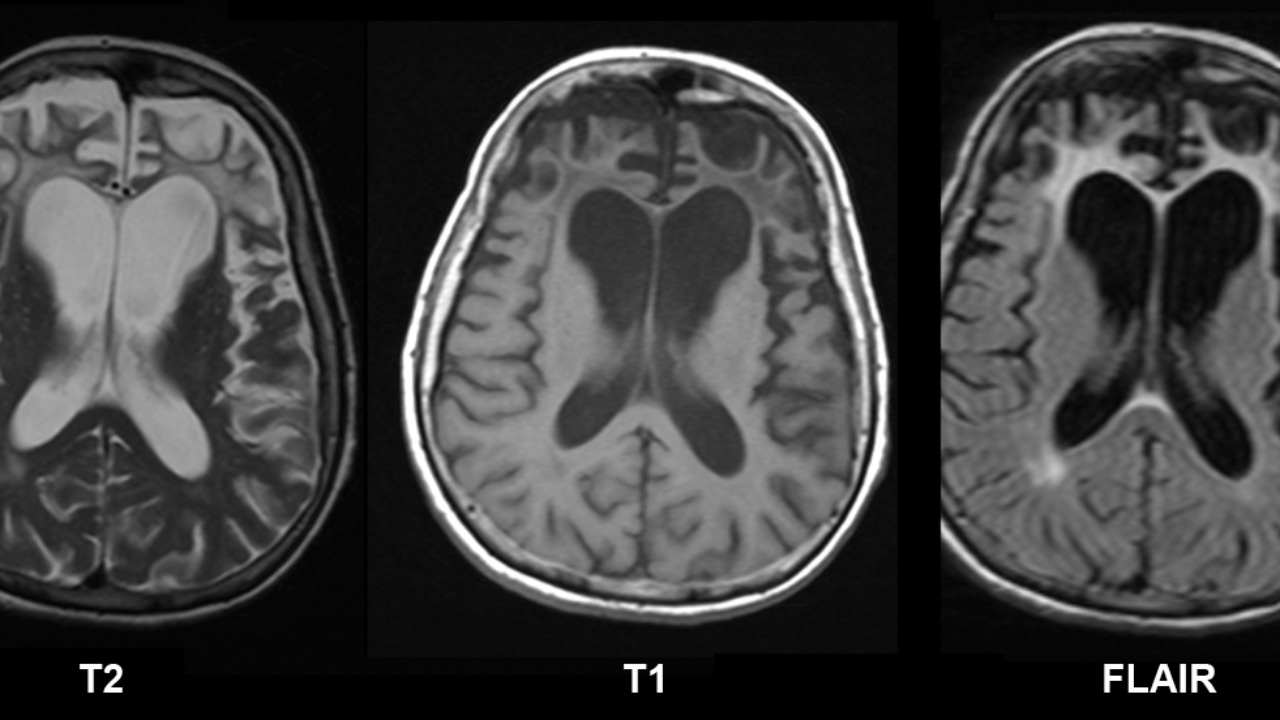

Compared to existing methods like MRI or PET scans, this new technique offers significant improvements in sensitivity and non-invasiveness. Traditional imaging methods often struggle to detect the subtle changes associated with early-stage FTD, leading to delays in diagnosis and treatment. By contrast, the new technique provides a more detailed and accurate picture of the brain’s condition, enabling clinicians to make informed decisions about patient care.